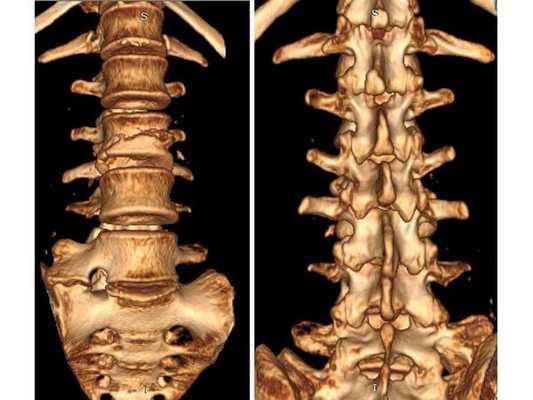

Пациентке проведена операция: транспедикулярная фиксация позвоночника L1-L4 и ламинэктомия L2 (удаление дужки позвонка с целью декомпрессии). Ход операции: • При положении пациентки лёжа на животе в проекции остистых отростков L1-L4 произведён прямой вертикальный разрез мягких тканей размером 10 см. • Надкостницы поперечных отростков и дугоотросчатых суставов отделены от костей. Кровотечение остановлено при помощи электрокоагуляции по ходу доступа. • Под контролем рентгена выявлены ножки L1 и L4 позвонков и сформированы каналы в тела самих позвонков, через которые в их ножки введены моноаксиальные педикулярные винты. • Проведена ламинэктомия позвонка L2. При ревизии твёрдой мозговой оболочки, окружающей спинно-мозговые корешки, на уровне L2-L3 позвонков обнаружены выраженные изменения рубцово-спаечного характера. • Рана промыта при помощи физраствора и раствора перекиси водорода. Поверх твёрдой мозговой оболочки уложена гемостатическая губка. Установлены две продольные штанги, закручены стопорные гайки. • В конце на рану наложен послойный шов нитью Викрил и асептическая повязка.

После операции в неврологическом статусе наблюдается положительная динамика: умеренный парапарез в нижних конечностях почти полностью регрессировал, жалобы на "онемения в ногах" также исчезли. На контрольной КТ видно состояние после успешной декомпрессии на уровне L2-L3 и установки транспедикулярной фиксирующей системы на уровне L1-L4.